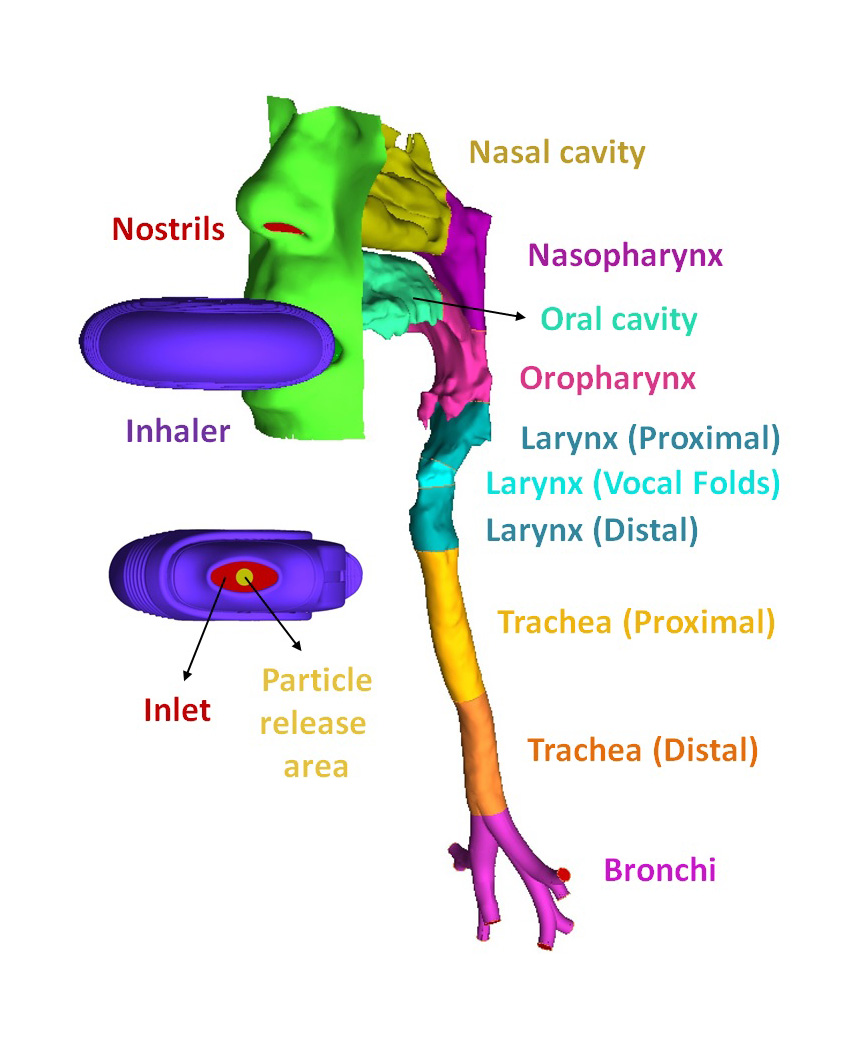

Search for PhD funding scholarships studentships in the UK Europe and around the world. CFD is capable of providing valuable hemodynamics which is useful in the clinical assessment of heart performance and the early diagnosis of heart dysfunction 3 6 7. The review then focuses on the applications of CFD in biomedical problems including cardiovascular diseases airflow pattern and aerosol deposition in lungs cerebrospinal fluid flow in brain and for artificial organ design analysis.

Respiratory Drug Delivery Airway Lab Joint Department Of Biomedical Engineering Marquette The Medical College Of Wisconsin